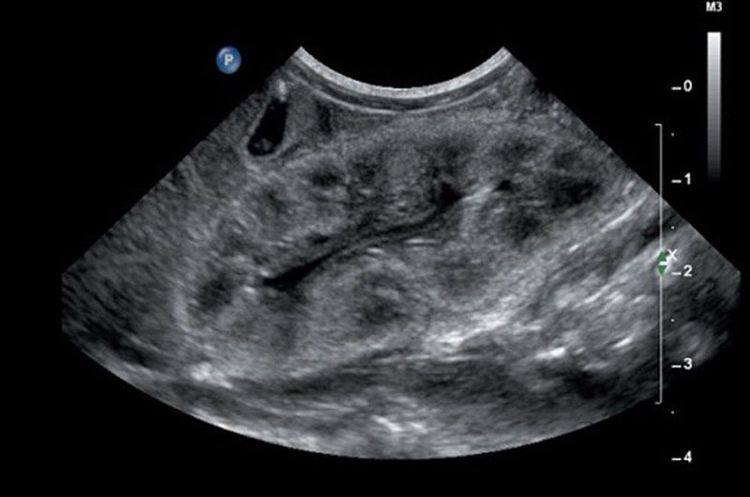

Siêu âm thận là phương pháp khảo sát hệ tiết niệu bằng sóng âm, khi phát sóng âm qua đầu dò vào các tạng trong ổ bụng sẽ thu về hình ảnh tại bộ xử lý hình ảnh, từ những hình ảnh đó để đưa ra các chẩn đoán bệnh lý nếu có bất thường.

- Thận nằm ở trong hố thắt lưng, trên mặt phẳng ngang có hướng chếch từ sau ra trước và từ ngoài vào trong. Khi siêu âm thận cần đánh giá theo hường cắt dọc và cắt ngang của thận để đánh giá được chức năng của thận.

- Khi siêu âm thận phải, bác sĩ thường dựa vào cửa sổ gan để thấy rõ được cực trên của thận và qua lát cắt dưới sườn đề thấy phần dưới của thận.

- Thận trái thường phải cắt theo hướng sau bên của thành bụng, do khó sử dụng được cửa sổ lách.

- Niệu quản là cấu trúc nối giữa thận và bàng quang, siêu âm thường thấy đoạn dưới bể thận và đoạn gần bàng quang. Tuy nhiên, thường khó quan sát và đánh giá trừ khi có những bất thường xảy ra. Bên cạnh đó, đánh giá bàng quang của người bệnh.